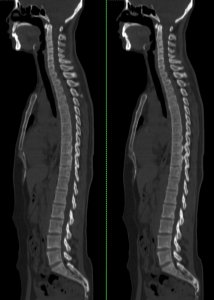

- 强直性脊柱炎到底是啥样?几张影像片清楚地告诉你